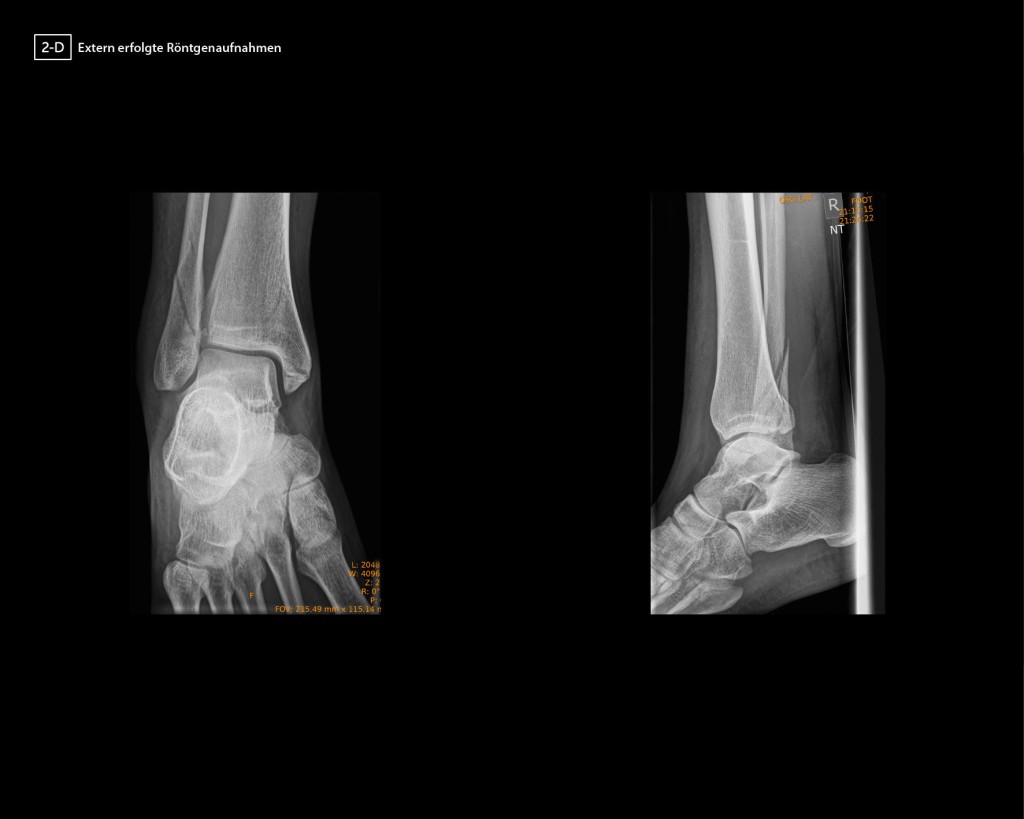

Vor den genannten Hintergründen ist das SCS DVT in der ATOS Klinik Wiesbaden fester Bestandteil des Diagnostikspektrums und wird auf Basis der beschriebenen Strahlenhygiene häufig mit dem SULD-Protokoll als Primärdiagnostik angewendet. Der Autor kann auf mehr als 11 Jahre Anwendungserfahrung zurückgreifen und von unzähligen Fällen berichten, in denen das DVT die entscheidenden Informationen zur Therapieplanung beigetragen hat. Beispielhaft soll dazu nachfolgend ein Fall vorgestellt werden. In dem dargestellten Fall zeigten die extern angefertigten 2-D-Röntgenbilder einer 27-jährigen Frau nach einem Distorsionstrauma eine Mehrfragmentfraktur der distalen Fibula mit fraglicher Beteiligung der Syndesmose, eine Fraktur des hinteren Volkmanndreiecks <1/4 der Gelenkfläche, sowie eine Fraktur des medialen Malleolus. In der AP-Projektion kommt eine Aufhellungslinie im Bereich der medialen Tibia zur Darstellung, die nicht exakt zuzuordnen ist und in der seitlichen Ebene kein entsprechendes Korrelat zeigt (Abb. 1).